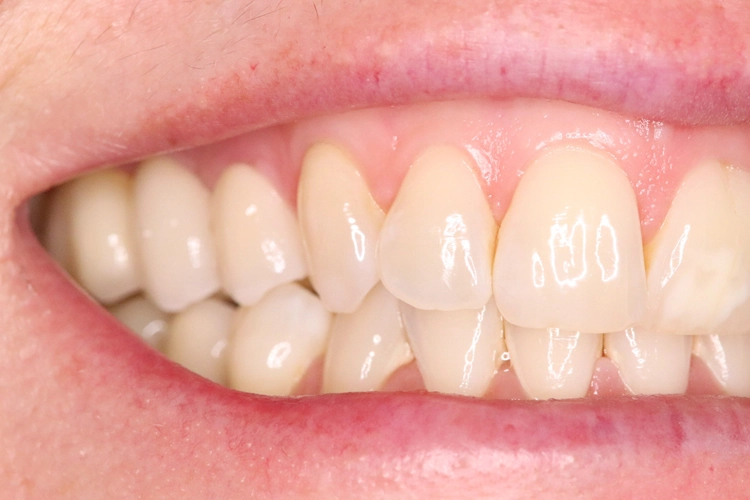

Das alte Titanimplantat (20 Jahre in situ) bekam auch einen Zirkonaufbau (Abb. 19). Nach drei Wochen erfolgte die defi nitive Versorgung mit nicht-verblockten Zirkonkronen (Abb. 20).

Kontrollbild und Röntgenkontrolle ein Jahr und ein Monat nach Socket/Ridge Preservation (Abb. 21 und 22). Der komplette Umbau zu Eigenknochen ist noch nicht abgeschlossen. Die Papillenregeneration zwischen 13/14 und 14/15 ist jedoch deutlich erkennbar.